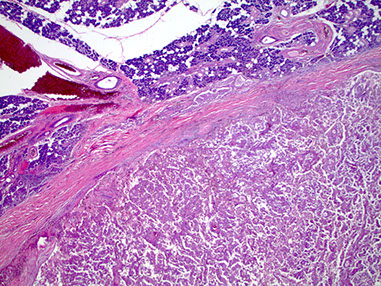

Sialoblastoma

Rare, sometimes aggressive tumor of major salivary glands, usually seen at birth and looks like primitary salivary development

- M=F, usually slow-growing,

- grosly multilobulated and at least a little circumscribed, sometimes c local invasion and hemmorhage, necrosis if higher grade

Px: recurs locally in 1/5